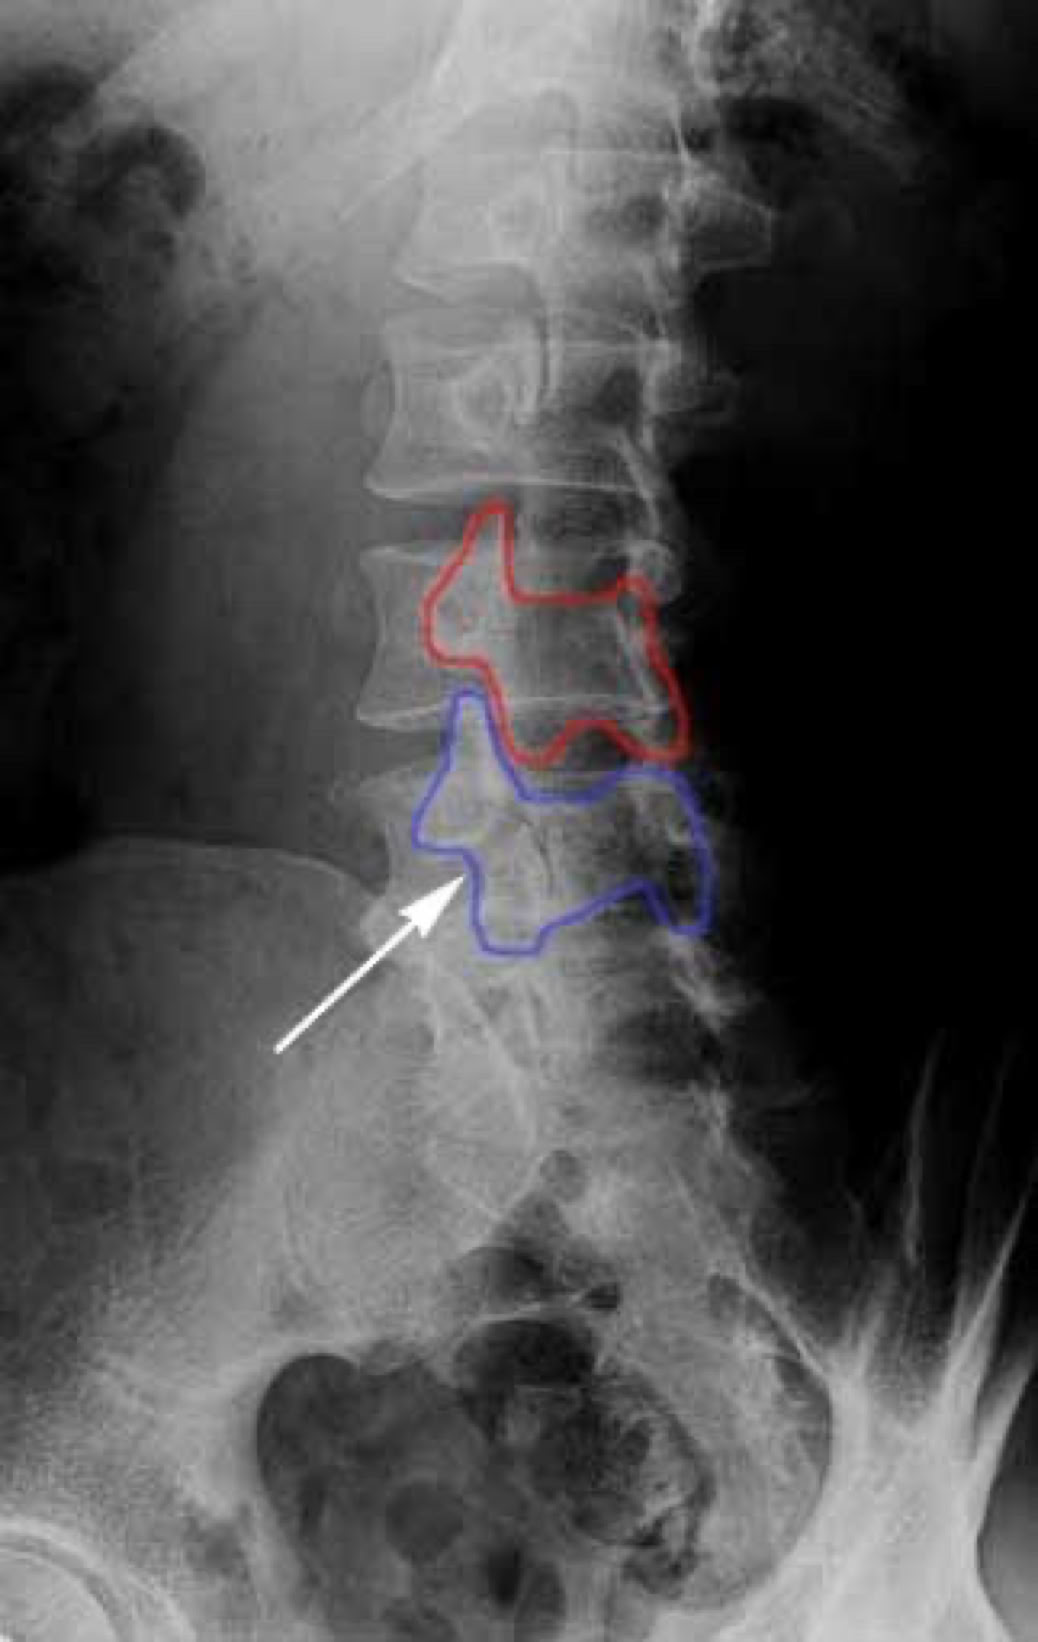

When we look at the spine from the side, we can imagine a scotty dog. It is outlined above. The pars fracture is seen as a collar around the dog's neck. Instability and movement can cause the neck to widen. We will see this below in an X-ray example.

X-RAY SHOWING A PARS FRACTURE DEFECT

THE WHITE OUTLINE SHOWS THE SLIPPAGE.